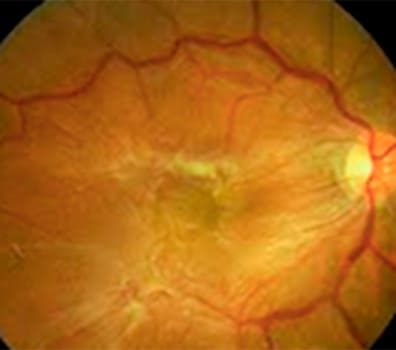

•Mapeamento de retina (fundo de olho)

•Retinografia colorida